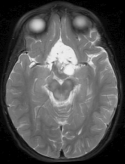

Table 2 shows the SNR values of the different reconstruction results. Figure 5 shows the reconstruction results at 5,10 and 16.6-fold acceleration of a patient with OPG. Both TCS-MRI and LACS-MRI exhibit almost no loss of information at 10-fold acceleration. Similar results are obtained with CS-MRI only at 5-fold acceleration.

This experiment shows that thanks to the ability to under-sample the 2D phase encode plane, the advantage of temporal similarity exploitation is emphasized. Therefore, LACS-MRI allows shortening the scanning time by a factor of 10, with no significant loss of information in this case.